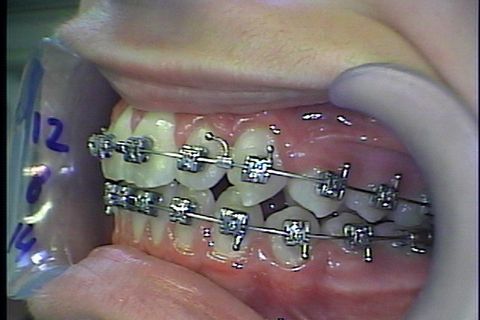

Fase final

Fase Final, intercuspidando e talvez haverá necessidade de desgastes interproximais devido a Bolton superior

Paciente Classe II, já havia usado disjuntor por falta de espaço, durante tratameto foi usado o Twin Force para projeção da arcada inferior e melhora do encaixe em Classe I de canino,na finalização do caso vemos que a paciente possui Bolton Superior o que provavelmente gerará a necessidade de desgastes interproximais para concluirmos com uma finalização adequada do caso.